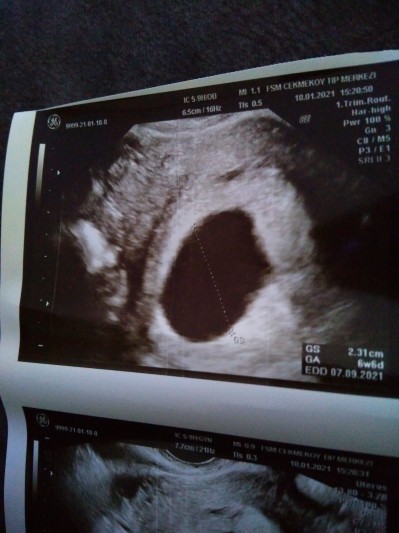

Adete göre 8+3 ultrasona göre  6+6 kese 23 mm vajinalle boş kese gözüküyor sadece başına gelen var mi